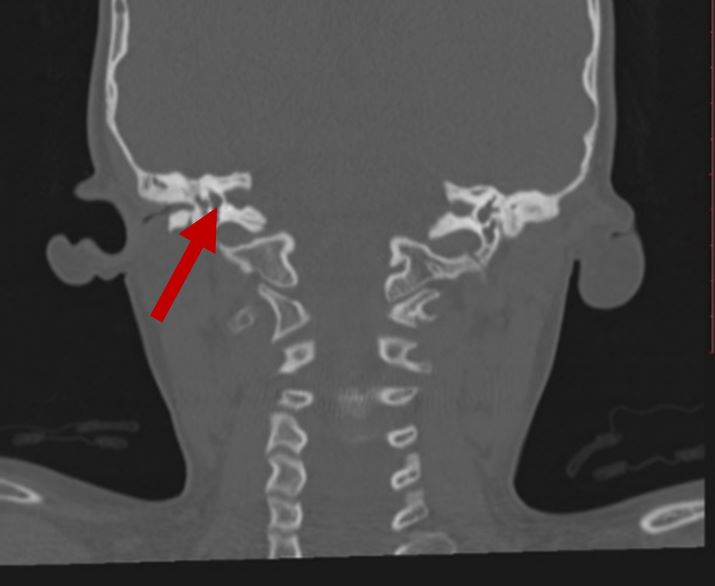

Fused vertebrae

2D CT scan showing fused 2nd and 3rd vertebrae

Radiographical features source 9